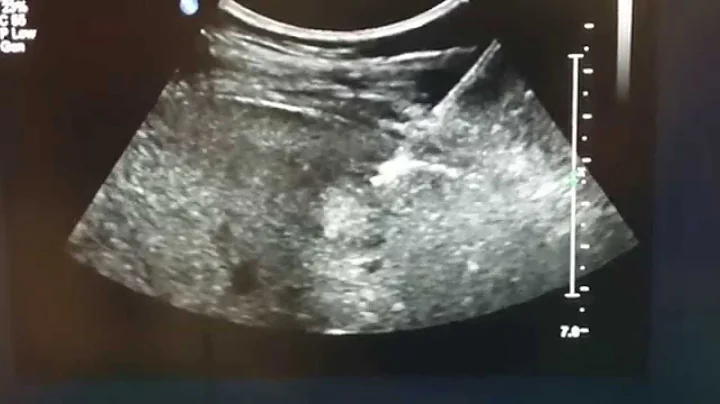

Canine Liver Fna Ultrasound

Demonstrates an example of fine needle aspiration of the liver with ultrasound.